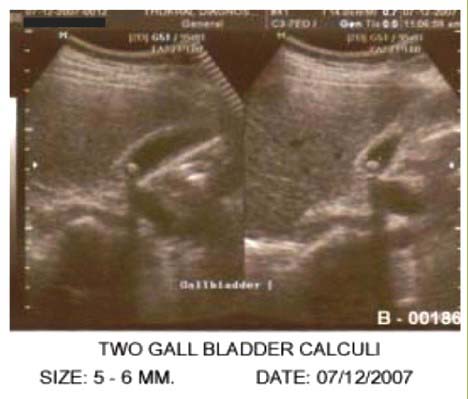

Patient was registered as a case of cholelithiasis on the basis of Ultrasonography of whole abdomen with multiple gall bladder calculi.

Initial Ultrasonography Report showed gall bladder normal in shape and place. Lumen shows multiple small stones.

Ultrasonography Report showed gall bladder is normal in shape and outline. Lumen shows two small calculi, measuring 0.5 & 0.6 mm in size near GB neck. The calculi are moving slightly with change in posture.